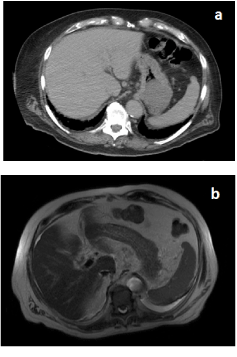

The patient is a 76-year-old Caucasian male presenting with progressive weakness, ambulatory dysfunction and mild anemia. CT of abdomen and pelvis revealed ascending colitis while liver, spleen, pancreas and adrenals appeared normal (Figure 1a). He was initially treated with antibiotics for colitis. His alkaline phosphatase and GGT levels were high up to 1200 U/L and 938 U/L respectively, SGPT was normal while SGOT was greatly elevated, suggestive of a common bile duct defect. MRCP, however, did not show any biliary duct dilation or filling defect within the biliary tree or any evidence of a pancreatic duct dilation (Figure 1b). Alpha fetoprotein level was normal (3.3 ng/ml). Colonoscopy was performed and a lesion highly suggestive of colon cancer was found in the ascending colon. The patient was admitted for surgery and further investigation.

Figure 1. Images showing no metastasis in liver or pancreas or biliary tract. [a) Abdominal CT; b) Abdominal MRI]